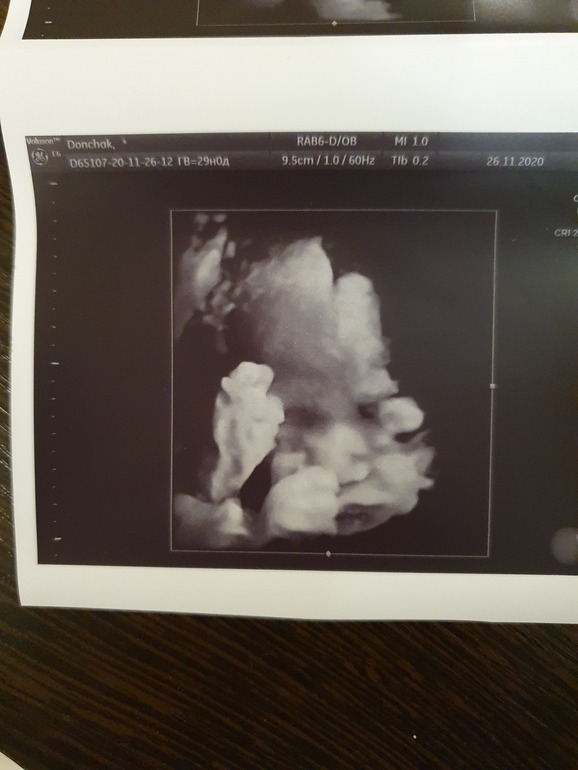

С сыном я тоже ходила, но не помню у себя таких эмоций, молодая, может была)))все у нас хорошо, кнопка такая, до этого на всех узи закрывала личико руками и ногой)и вчера у лица и нога и рука,но не закрылась, дала на себя посмотреть)гиперэхогенный фокус в сердце ушёл, слава Богу🙏в принципе, я уже и успокоилась, все сказали, и врачи, и тут на ББ, что это не страшно, но все равно, так гораздо спокойнее мне. Декрет мне передвинуть с 3 на 9 декабря, так как цикл нестабильный, посчитали ПДР по первому скринингу. Вес 1450))

Ну и фоточки наши)

А это моя кнопочка